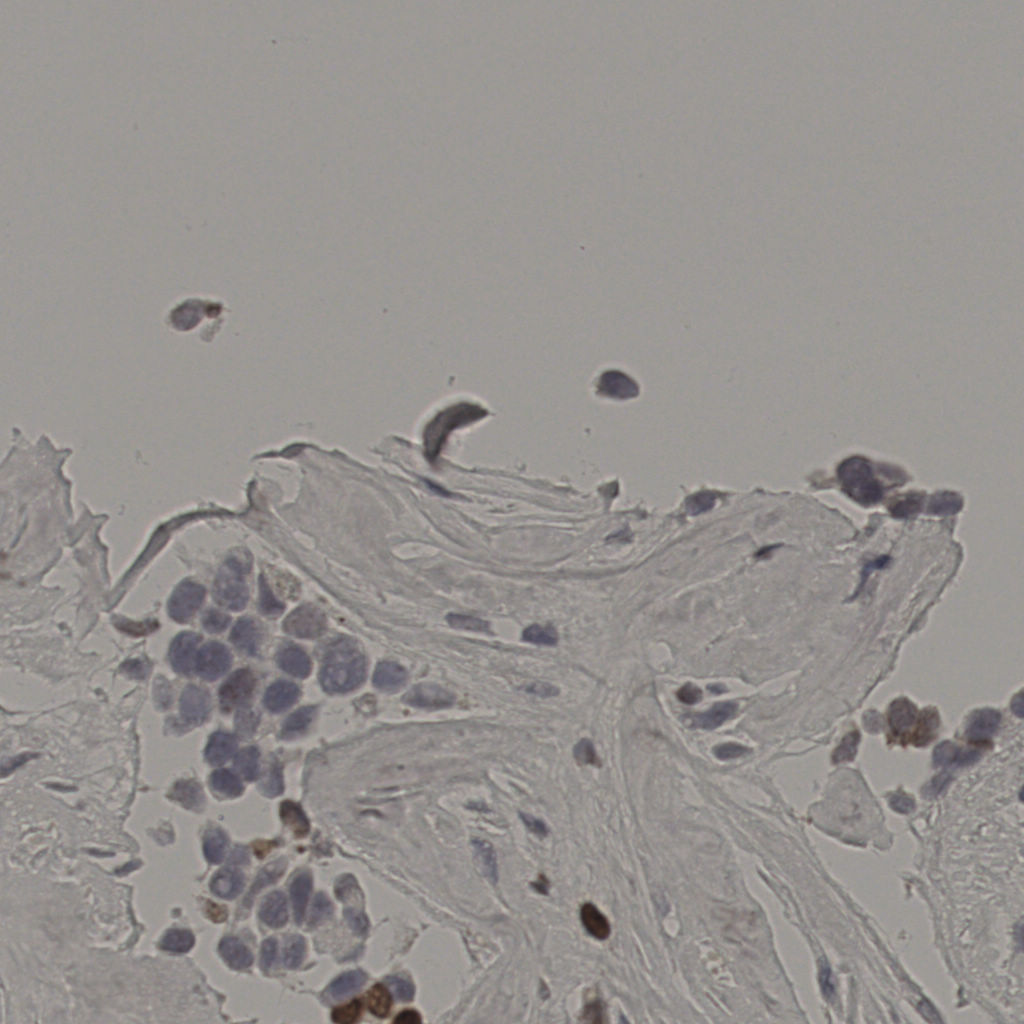

17.75%

Ki67 指数

阴 7986 阳 1723

总切片 2640

有效 412

已标记 412

有效率 16%